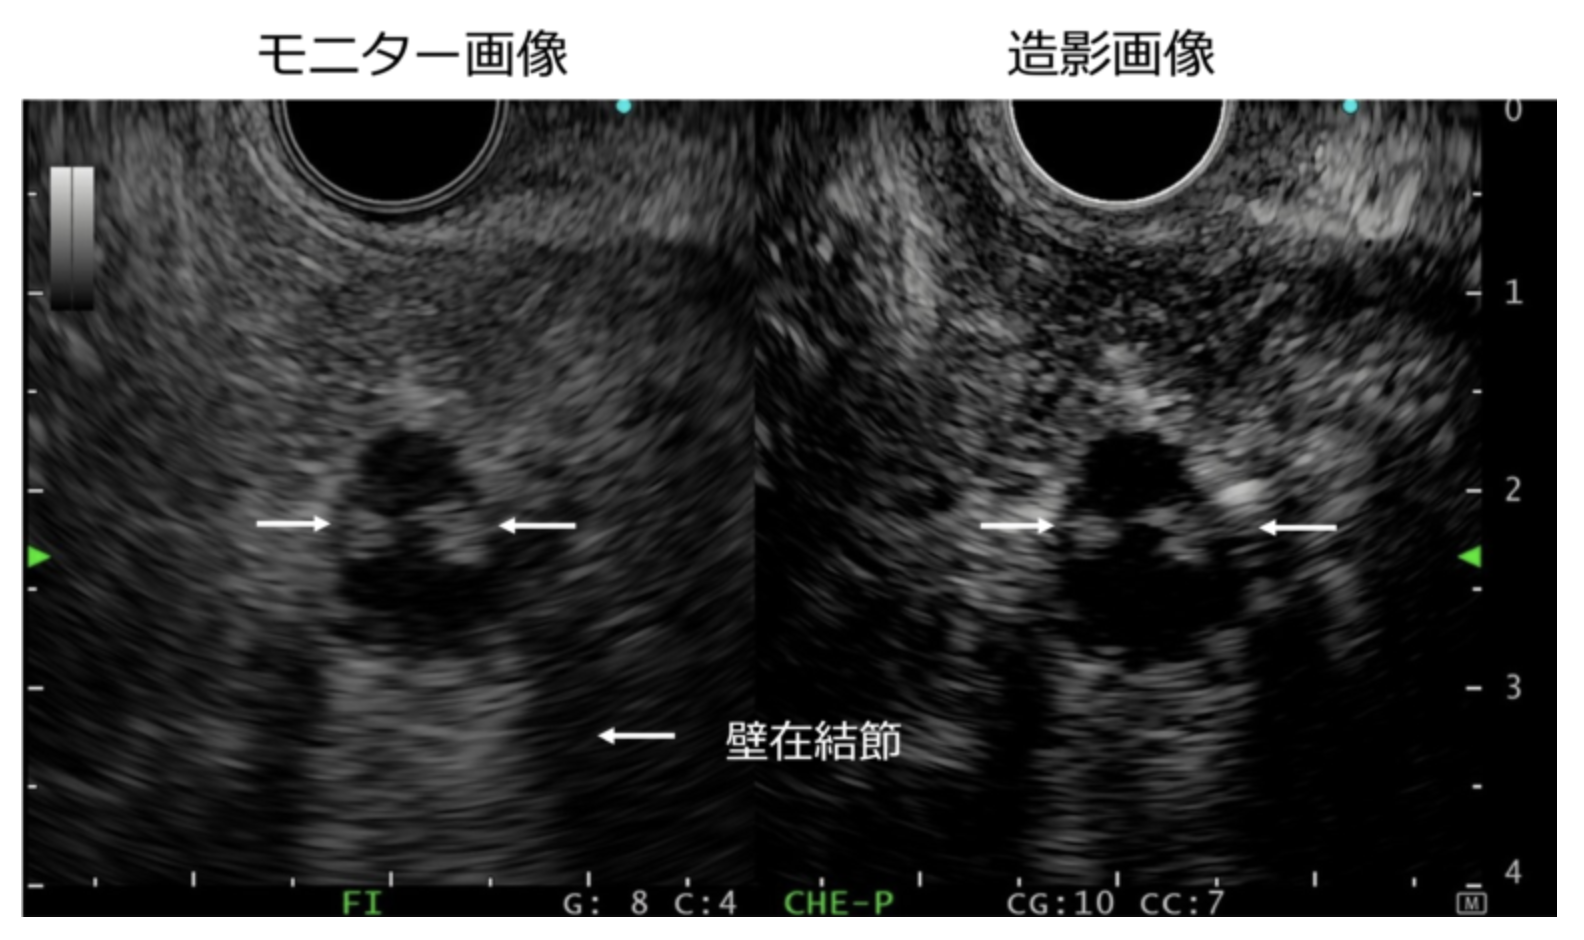

<造影超音波内視鏡検査>

(東京女子医科大学消化器内科 白田 龍之介先生(当院非常勤)ご提供)

造影画像(右側)で、壁在結節が白く造影されているのがわかります。

*日本では超音波内視鏡検査時の造影剤の使用は、健康保険で認められていません(2024年11月3日現在)。